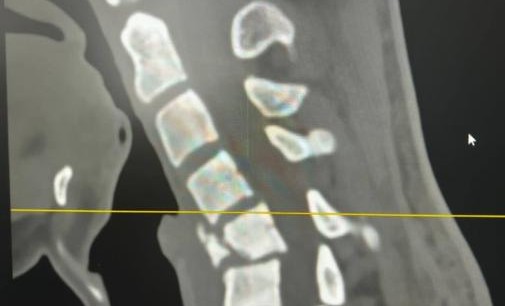

В Республиканскую клиническую больницу им. Ш.Ш. Эпендиева экстренно был доставлен пациент, который после неудачного падения на спину стал ощущать сильную слабость во всём теле и боль в шейном отделе позвоночника. У больного также наблюдалась неврологическая симптоматика: онемение в руках и ногах с нарушением двигательных возможностей конечностей. После проведенного КТ-исследования выявили выраженный перелом 5 позвонка шейного отдела позвоночника с миграцией отломков и деформацией шейного отдела.